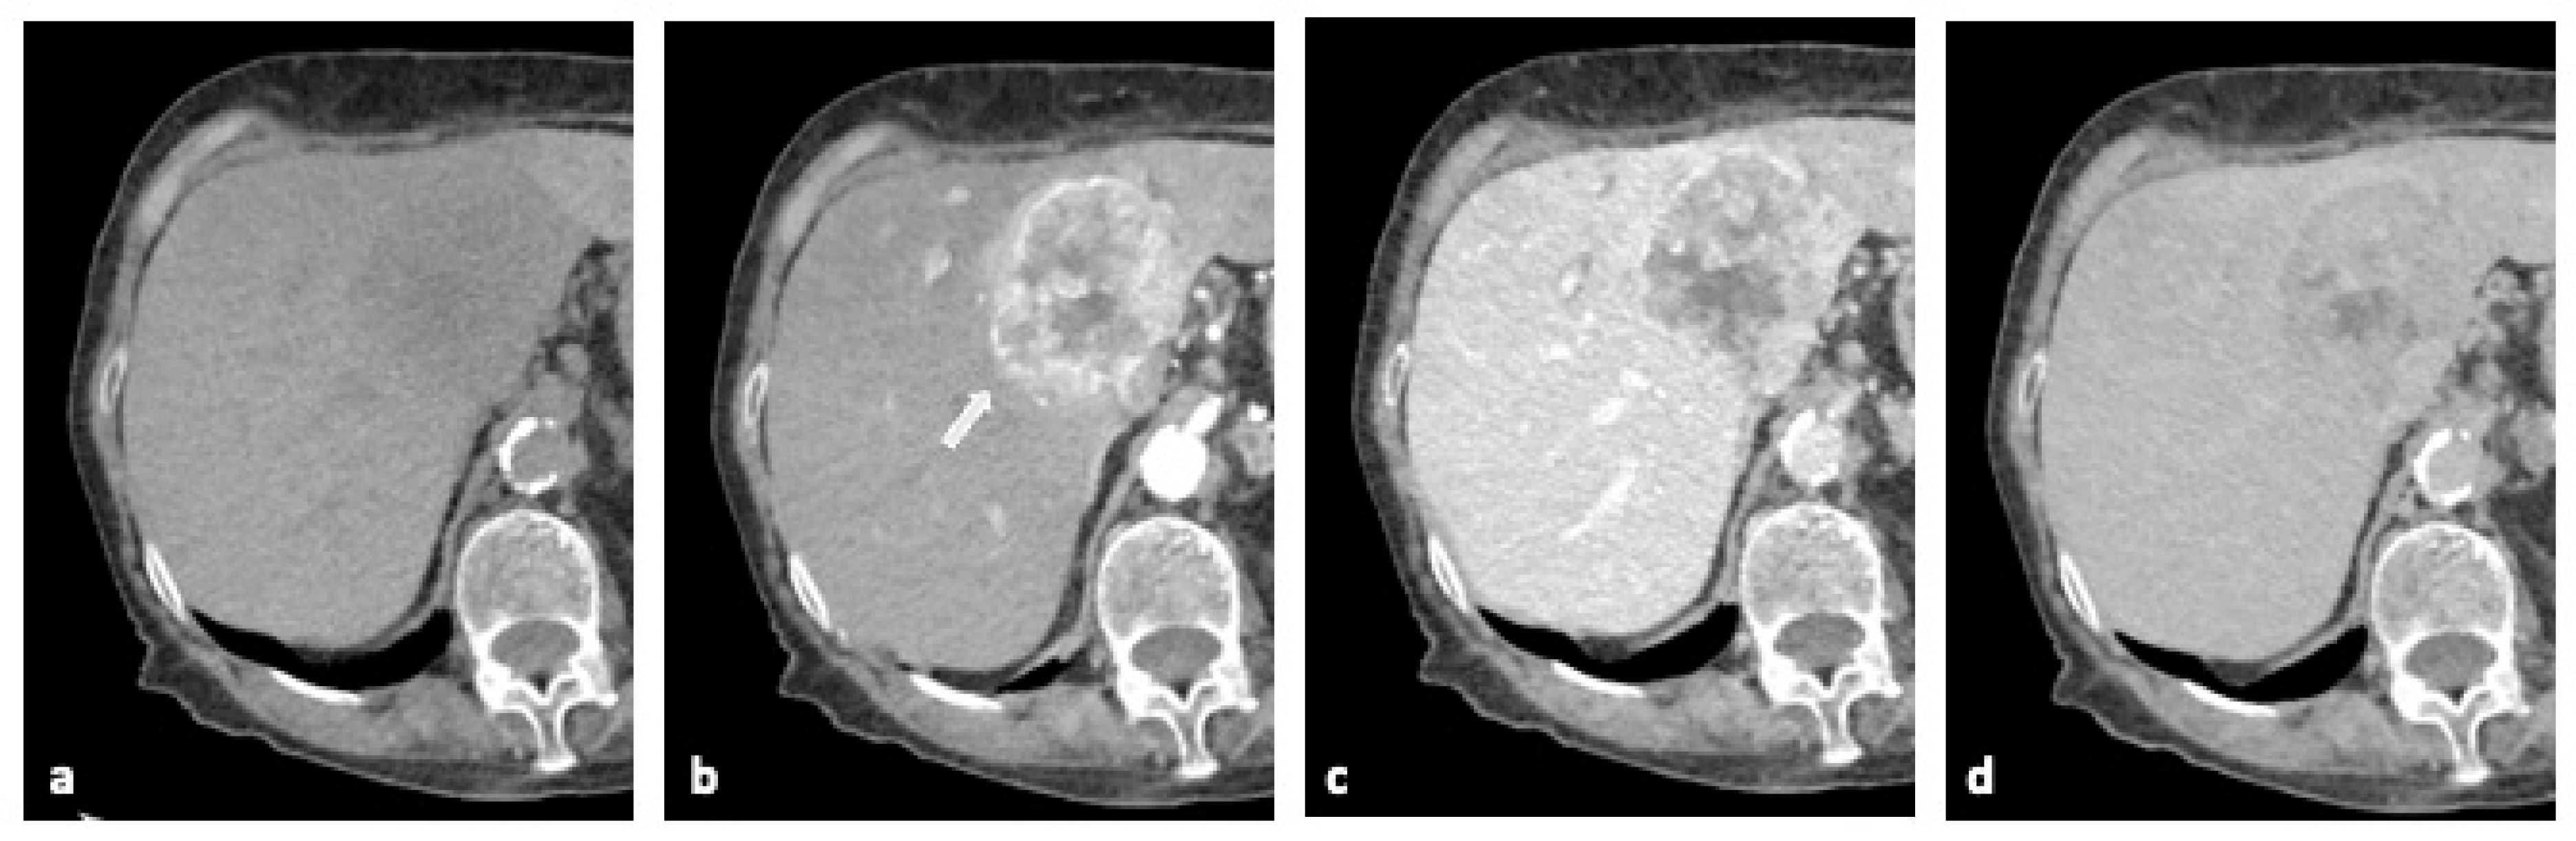

2.2. Computed Tomography (CT)

| Computed Tomography (CT) | High spatial resolution, good for staging and assessing vascular invasion. | Radiation exposure and limited soft tissue contrast. | 80–90% | 70–85% | 75–85% | 80–90% |